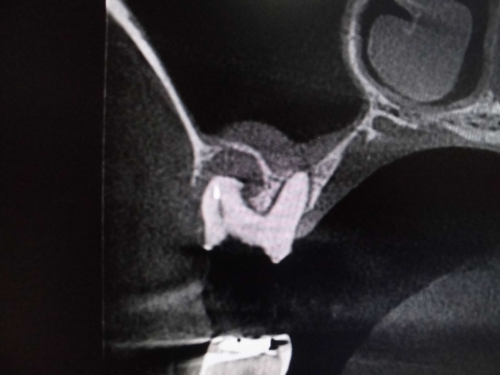

上顎洞との位置関係が確認できます。

CTでは近心の第二根管も確認できます。